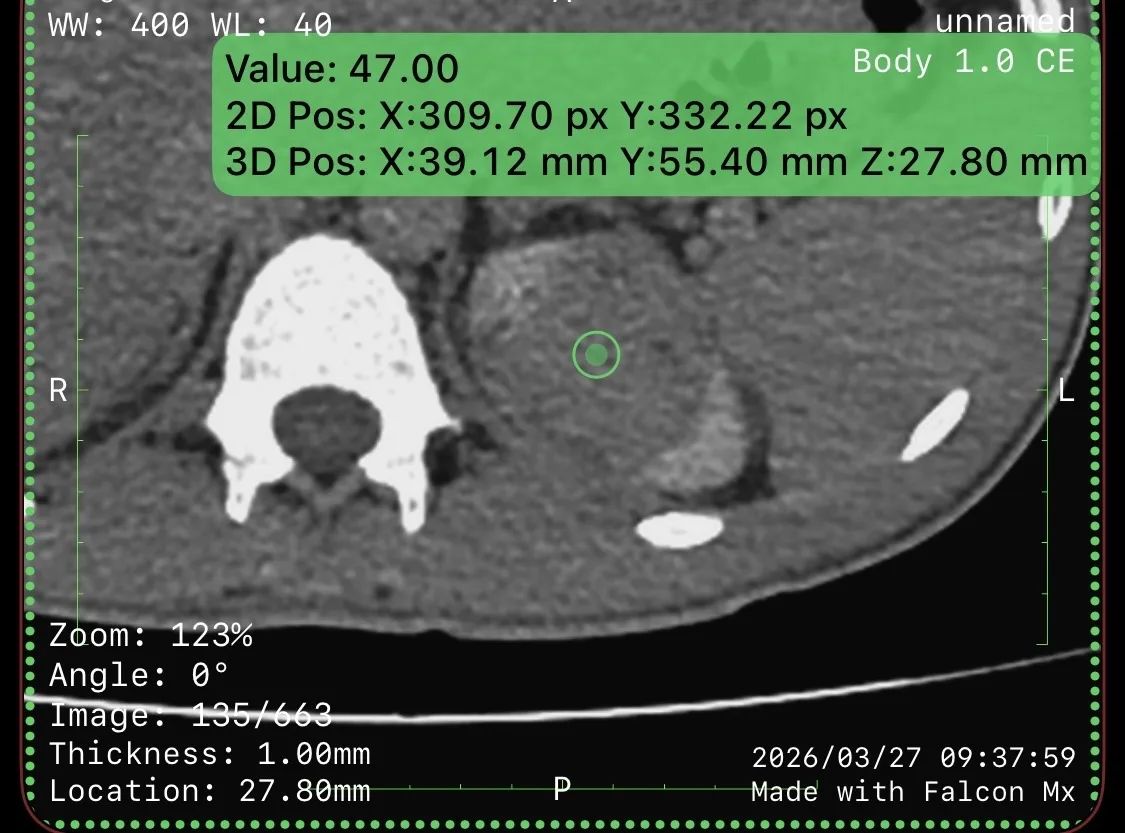

Пациент 27 лет. Две недели назад ударно-волновая литотрипсия. Неделю назад резкое повышение температуры тела, боли в боку. Повторная госпитализация. Установлен стент в левый мочеточник. Нарушения оттока мочи нет. На компьютерных томограммах левосторонний бактериальный нефрит, в верхнем полюсе левой почки – то, что иногда называют карбункул: воспалительный инфильтрат без формирования абсцесса (в англоязычной литературе называется нефрония). Принято решение продолжать антибиотикотерапию.